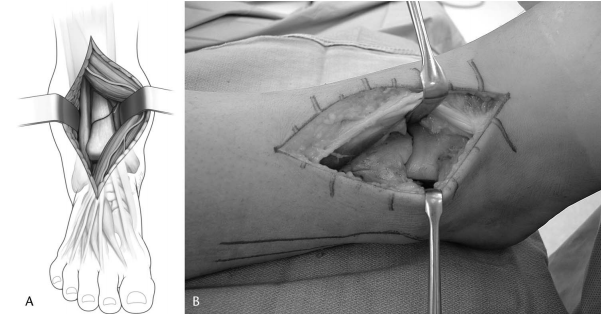

可以在或接近前外侧骨折线处进行关节切开术,以避免破坏远端胫骨的血供(图 3)。应注意不要切开胫腓前韧带。通过向远端延伸关节切开术至距骨颈,并将关节囊从胫骨远端前部抬起,可以实现对关节骨块的直视。

图 3. (A) 示意图和 (B) 临床照片,显示前外侧入路的深层显露,腓浅神经及前间室肌肉肌腱向内侧牵开,显露胫骨远端关节面。

关节面的可视化和重建可以通过应用基于外侧的通用撑开器进一步得到增强(图 4)。将一根 4 毫米施氏针置于距骨颈。第二根 4 毫米施氏针经前间室上方一个单独的小切口,从外侧置入胫骨近端,预计的接骨板位置近端。这个近端施氏针的置入可能使前神经血管束和/或腓浅神经处于风险之中。通过将螺纹杆置于后外侧,通用撑开器本身不会妨碍复位或成像,并且力矢量将使距骨撑开和跖屈,从而最大化从前到后的关节可视化。

图 4. (A) 示意图详细说明了将通用撑开器应用于胫骨远端外侧,胫骨近端置入施氏针,距骨颈置入施氏针。(B) 如侧位 X 光片所示,允许对关节面进行可视化。